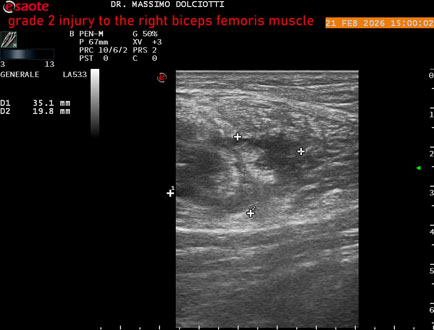

Ecografia del: 21/02/2026

Età Paziente: M 49 anni

Motivazione dell'esame: da 10 giorni dolore insorto durante la corsa.

Commento all'esame: le immagini ed il video documentano, al muscolo bicipite femorale destro, in sede prossimale, area disomogenea, ipoecogena, delle dimensioni di 27 x 24 mm (misura ottenuta per asse corto o trasversale) e delle dimensioni di 51 x 33 mm (misura ottenuta per asse lungo o longitudinale), da ricondurre a lesione muscolare di 2° grado con modica raccolta sieroematica intramuscolare.

Conclusioni: lesione di 2° grado al muscolo bicipite femorale destro (grade 2 injury to the right biceps femoris muscle).